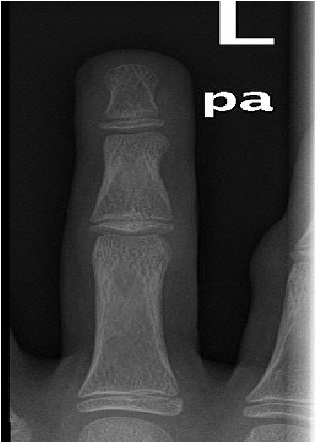

The Rise of Hoverboard Related Finger Injuries

Salim Al Lahham*, Rehan Zahid, Shiyas Mohammedali, Mutaz Abuelgasim, Mahmoud El Sharkawy, Ruba Sada, Talal Al Hetmi